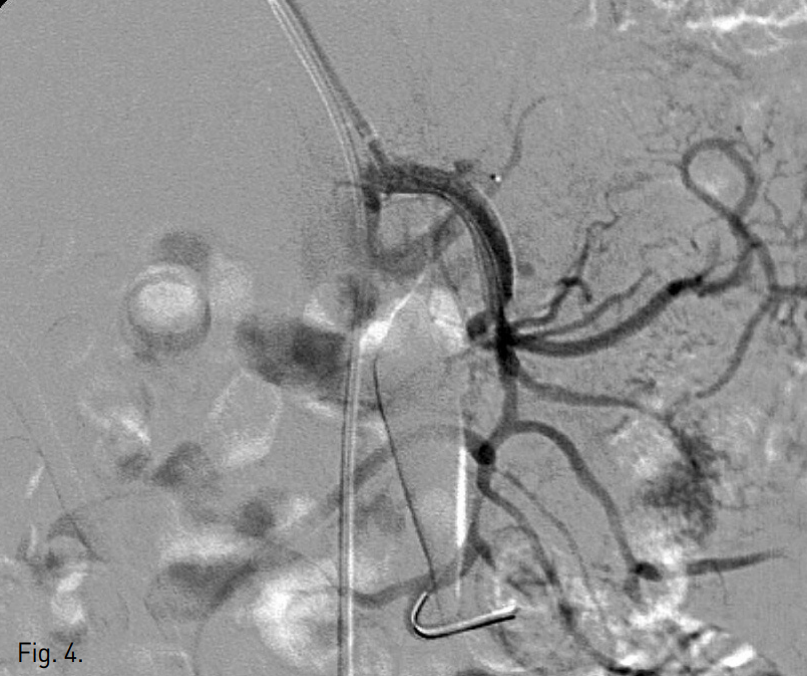

이어서 초음파 유도 하에 우측 상완동맥을 micropuncture introducer set (Cook, Bloomington, IN, USA)으로 access 후 6F sheath(Terumo, Tokyo, Japan)를 거치하고, 6F multipurpose guiding catheter (MPA1, Cordis, Miami, FL, USA)를 사용하여 상장간막동맥 기시부에 접근하였다. 이를 통해 0.014 inch microwire를 상장간막동맥 jejunal branch까지 insertion하고, microwire를 따라 6mm x 4cm self expandable stent (Precise PRO Rx, Cordis, Miami, FL, USA)를 dissecting aneurysm 입구를 포함하여 상장간막동맥 근위부에 deploy하였다(Fig. 4).

Fig. 4

A 6mm x 4cm self-expandable nitinol stent was placed in the true lumen of proximal SMA. The neck of dissecting aneurysm was fully covered by the stent.